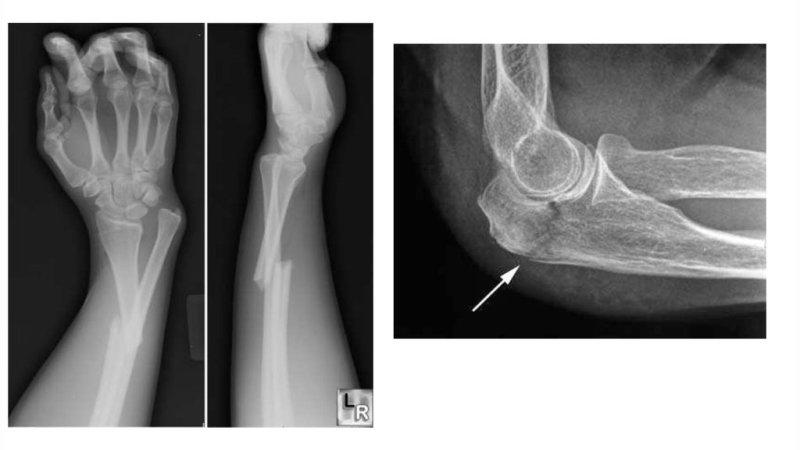

Анатомия знакома далеко не со всеми особенностями тела, но имеющиеся знания позволяют выделить основную систему строения, а именно опорно-двигательный аппарат. В его состав входит предплечье, которое закреплено локтевым суставом и суставом запястья. Данная область подвергается различным повреждениям, но большинство пациентов поступает с жалобами на перелом предплечья со смещением (фото см. ниже).

Врач сможет поставить диагноз уже после клинического обследования, который заключается в пальпации травмы, внешнем осмотре и беседе с пациентом. Однако, для постановки заключительно верного диагноза необходимо проведение рентгенологического исследования.

Также необходимо диагностировать наличие переломных вывихов, так как игнорирование повреждения капсулы локтевого сустава может нести за собой неприятные последствия.